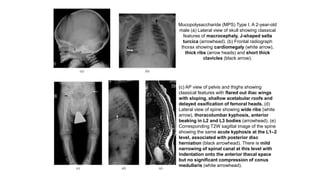

Mucopolysaccharide (MPS) Type I. A 2-year-old

male (a) Lateral view of skull showing classical

features of macrocephaly, J-shaped sella

turcica (arrowhead). (b) Frontal radiograph

thorax showing cardiomegaly (white arrow),

thick ribs (arrow heads) and short thick

clavicles (black arrow).

(c) AP view of pelvis and thighs showing

classical features with flared out iliac wings

with sloping, shallow acetabular roofs and

delayed ossification of femoral heads. (d)

Lateral view of spine showing wide ribs (white

arrow), thoracolumbar kyphosis, anterior

beaking in L2 and L3 bodies (arrowhead). (e)

Corresponding T2W sagittal image of the spine

showing the same acute kyphosis at the L1–2

level, associated with posterior disc

herniation (black arrowhead). There is mild

narrowing of spinal canal at this level with

indentation onto the anterior thecal space

but no significant compression of conus

medullaris (white arrowhead).